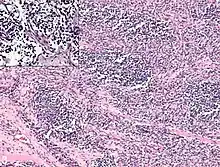

It is generally considered to be a disease of childhood, as the vast majority of cases occur in those below the age of 18. It is commonly described as one of the small-blue-round-cell tumors of childhood due to its appearance on an H&E stain.[4] Despite being relatively rare, it accounts for approximately 40% of all recorded soft-tissue sarcomas.[5][6][7]

Rhabdomyosarcoma is often difficult to diagnose due to its similarities to other cancers and varying levels of differentiation. It is loosely classified as one of the small-blue-round-cell tumors due to its appearance on an H&E stain. Other cancers that share this classification include neuroblastoma, Ewing sarcoma, and lymphoma, and a diagnosis of RMS requires confident elimination of these morphologically similar diseases.[15] The defining diagnostic trait for RMS is confirmation of malignant skeletal muscle differentiation with myogenesis (presenting as a plump, pink cytoplasm) under light microscopy.[5] Cross striations may or may not be present. Accurate diagnosis is usually accomplished through immunohistochemical staining for muscle-specific proteins such as myogenin, muscle-specific actin, desmin, D-myosin, and myoD1.[26][35][36] Myogenin, in particular, has been shown to be highly specific to RMS,[37] although the diagnostic significance of each protein marker may vary depending on the type and location of the malignant cells. The alveolar type of RMS tends to have stronger muscle-specific protein staining. Electron microscopy may also aid in diagnosis, with the presence of actin and myosin or Z bands pointing to a positive diagnosis of RMS.[5][35] Classification into types and subtypes is accomplished through further analysis of cellular morphology (alveolar spacings, presence of cambium layer, aneuploidy, etc.) as well as genetic sequencing of tumor cells. Some genetic markers, such as the PAX3-FKHR fusion gene expression in alveolar RMS, can aid in diagnosis. Open biopsy is usually required to obtain sufficient tissue for accurate diagnosis. All findings must be considered in context, as no one trait is a definitive indicator for RMS.